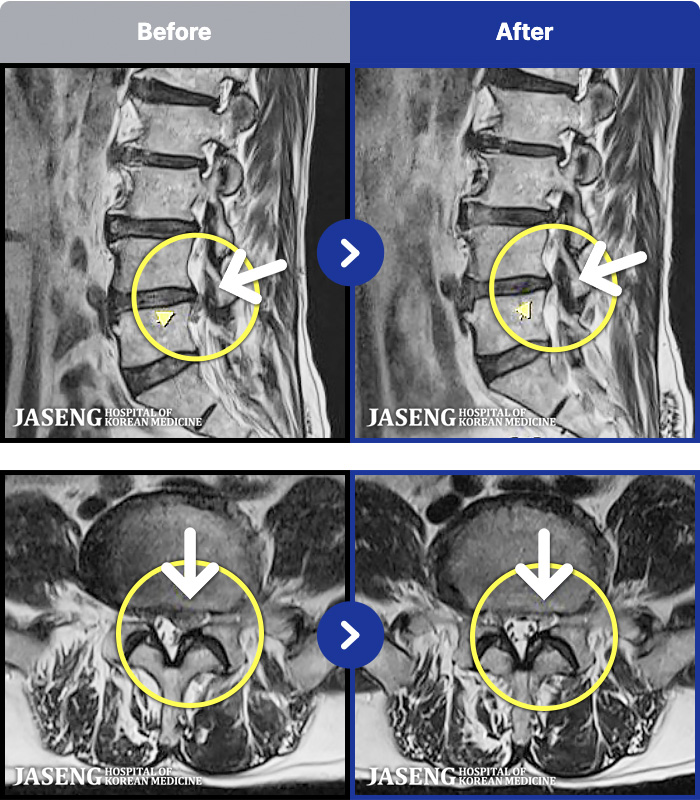

96 MRI ũ ʸ Ȯϼ.